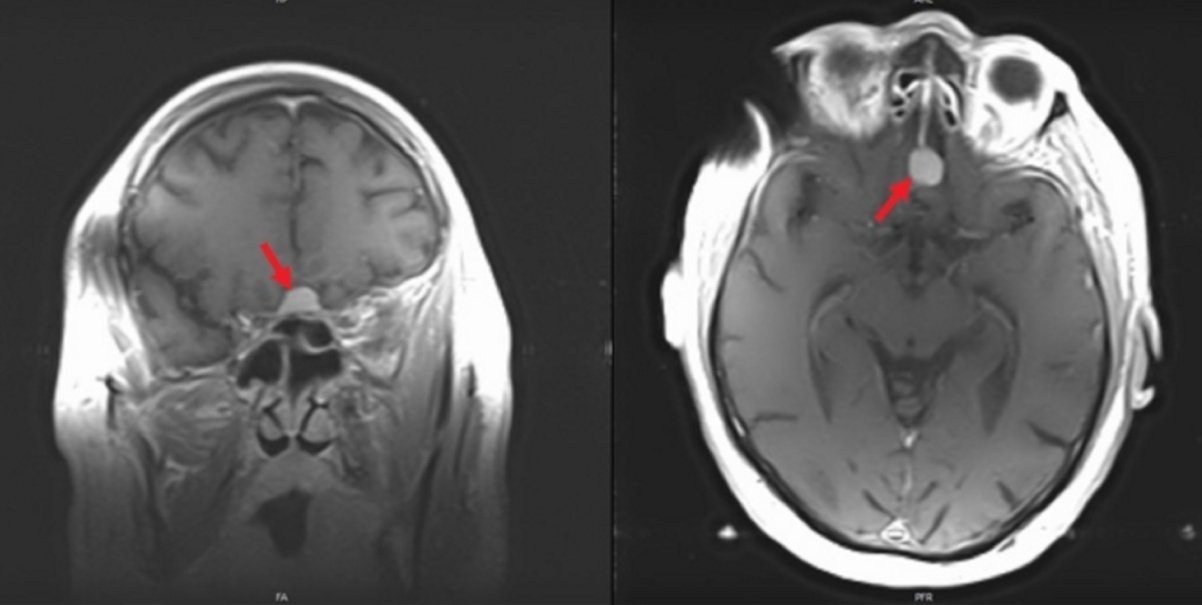

This patient has a primary CNS lymphoma. The presence of EBV DNA in the CSF is specific for this condition. MRI reveals a weakly ring-enhancing mass that is usually solitary and periventricular.

Toxoplasmosis is a good differential diagnosis; however, it is unlikely in this patient since he is receiving trimethoprim-sulfamethoxazole. MRI reveals multiple, ring-enhancing, spherical lesions in the basal ganglia. A positive Toxoplasma serology is quite common in normal subjects in the United States, and is therefore not specific for toxoplasmosis.